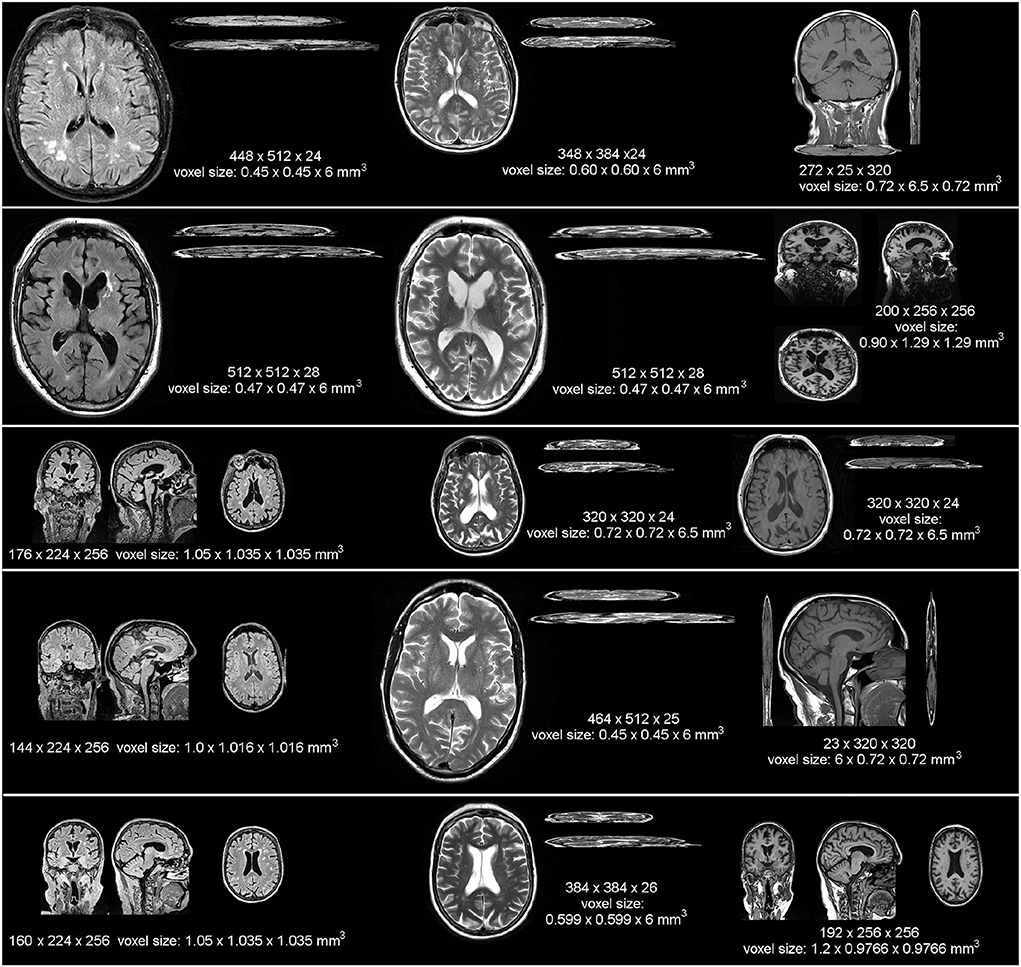

From index.mirasmart.com

Table 1 MRI scan protocols How To Calculate Mri Scan Time Each scan may take from seconds to about 4 minutes, according to the national health service. The radiographer may ask you to hold your breath during some. In addition to the basic resolution, image quality can be manipulated by changing the phase resolution. Or m imaging with normal pulse seuences, this can be easil calculated the acquisition time (at) is:. How To Calculate Mri Scan Time.